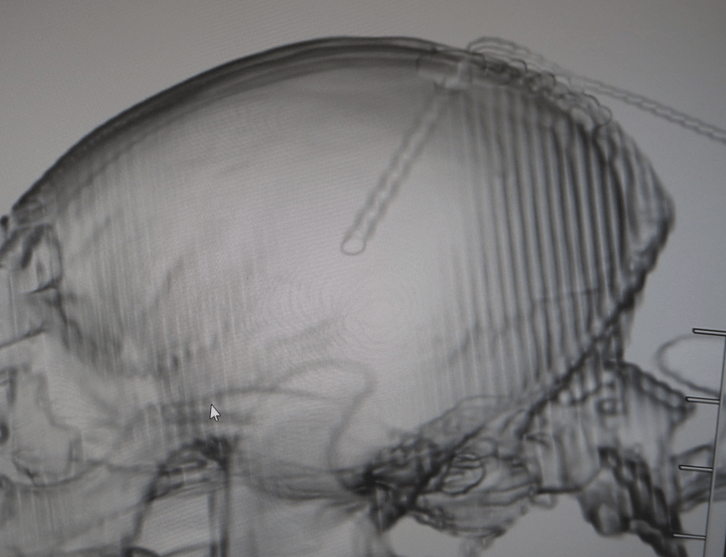

重松は何科でもなく、気持ち的にはなんでもまんべんなくなので、椎間板ヘルニアが緊急脊髄減圧科なら、V-Pシャントで脳圧も下げに行く事もあります。

同じように、椎弓切除からの椎体固定と同じノリで、開頭してプレートいれてしまう事もあります。これは神経科というか腫瘍科根性でしょうか。リハビリのヤツと同じで、意味のない称号かなんかわからん腫瘍科認定医もあまり好きではないです。一部だと思うんですけど全然腫瘍とらん腫瘍科もいます。